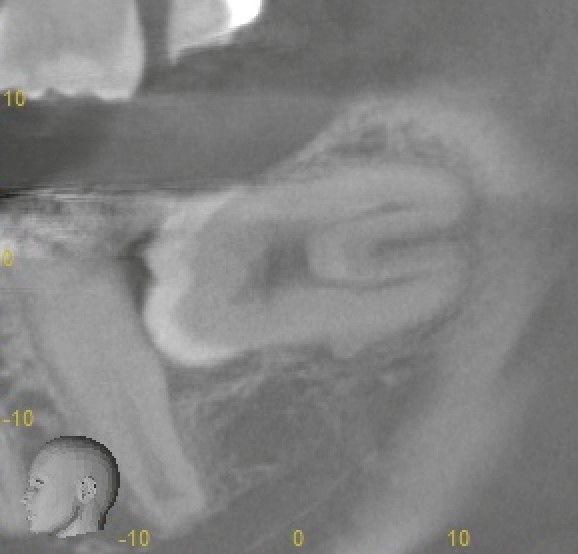

③ 下歯槽神経との距離が近づく

歯根が長くなるほど、

下歯槽神経に近接するリスクも高まります。

そのため、

* 術前CTによる立体的評価

* 抜歯手技の選択

* 力のコントロール

が不可欠になります。

実際の抜歯経過

上下ともに抜歯を行いました。

特に下顎の親知らずは、

* 麻酔の確認

* 慎重な歯根分割

* 神経への十分な配慮

を要し、

通常15分程度で終わる抜歯が、約30分かかるケースとなりました。

結果として、

* 歯根はきれいに抜去

* 神経症状なし